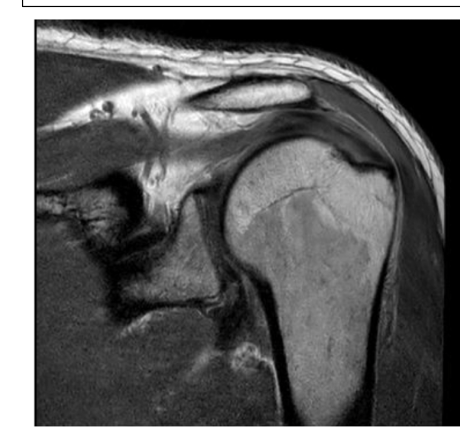

What are the sequences and what is the pathology?

• T1, STIR, T1FS C+

• Tissue lipoma- benign tumour made of fat tissue